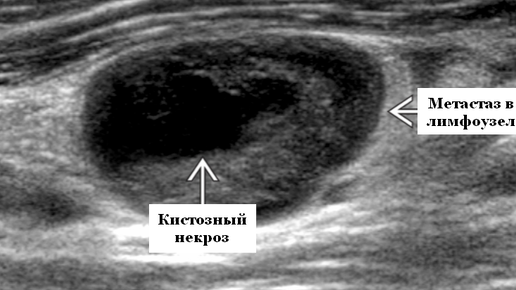

Что такое лимфоузлы и зачем они нужны? Лимфатические узлы — это маленькие фильтры в нашем организме, которые задерживают вирусы, бактерии и даже раковые клетки. В норме размер лимфоузлов не превышает 1–1,5 см, они мягкие, безболезненные и чаще всего незаметны. Но когда человек заболевает, лимфоузлы меняются — увеличиваются, уплотняются или становятся болезненными. Ультразвуковое исследование (УЗИ) — это безопасный и точный метод диагностики, который позволяет оценить структуру лимфоузлов без разрезов и проколов...